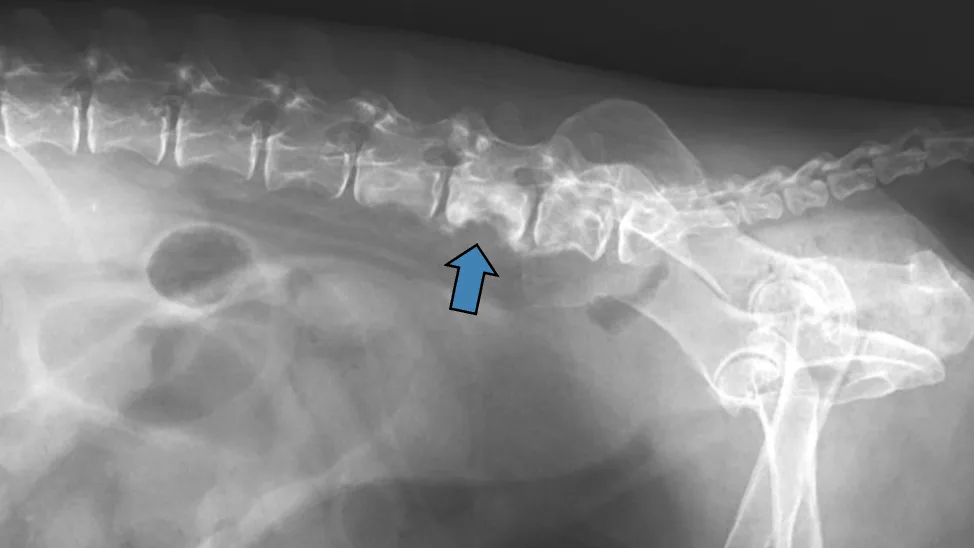

胸部/骨レントゲン検査

肺転移や骨転移の有無を評価します。